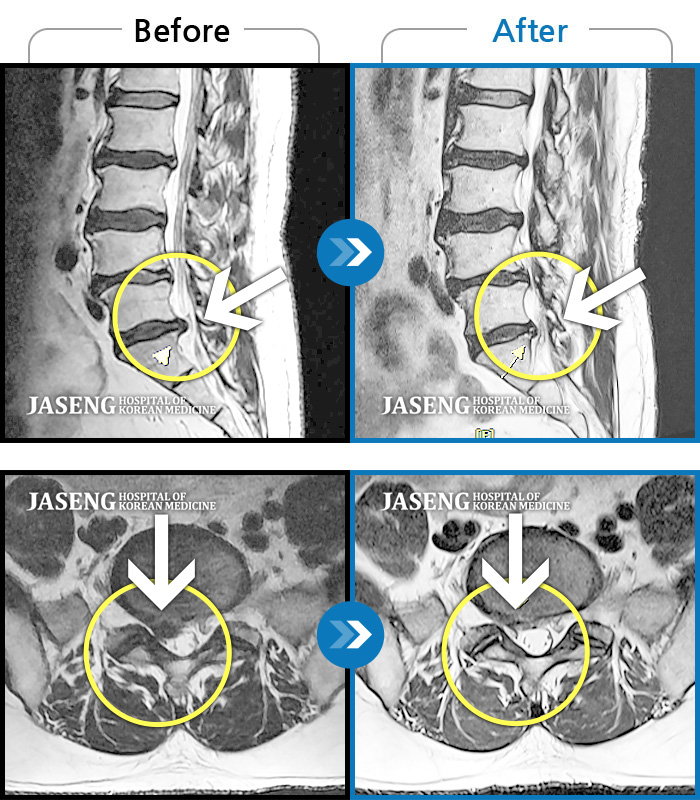

허리디스크

광주 · 장영우 원장

허리 양측부터 골반까지 통증, 우측 하지 외측으로 이어지는 저린감

촬영시기

2020.11.12 ~ 2021.10.18

2021.10.22